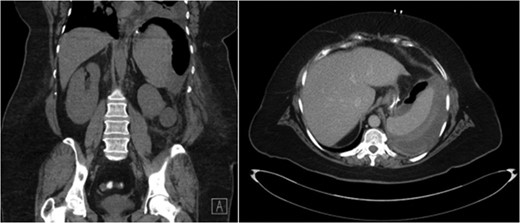

Unfortunately, she presented once more, 20 days after the initial operation with symptomatic hypotension and complaints of severe left upper quadrant pain after a fall in her home. CT scan demonstrated extravasation of intravenous contrast into the peritoneum as well as free intra-peritoneal air (Fig. 2). Given her hemodynamic instability and splenic injury, she was immediately taken to the operating room and underwent an open splenectomy. At the time of splenectomy, only old clotted blood was noted without evidence of purulent fluid or infection. She had a prolonged hospital course but was eventually discharged to a rehabilitation facility.

CT abdomen demonstrating extravasation of contrast and free intra-peritoneal air, with the absence of subcapsular air.